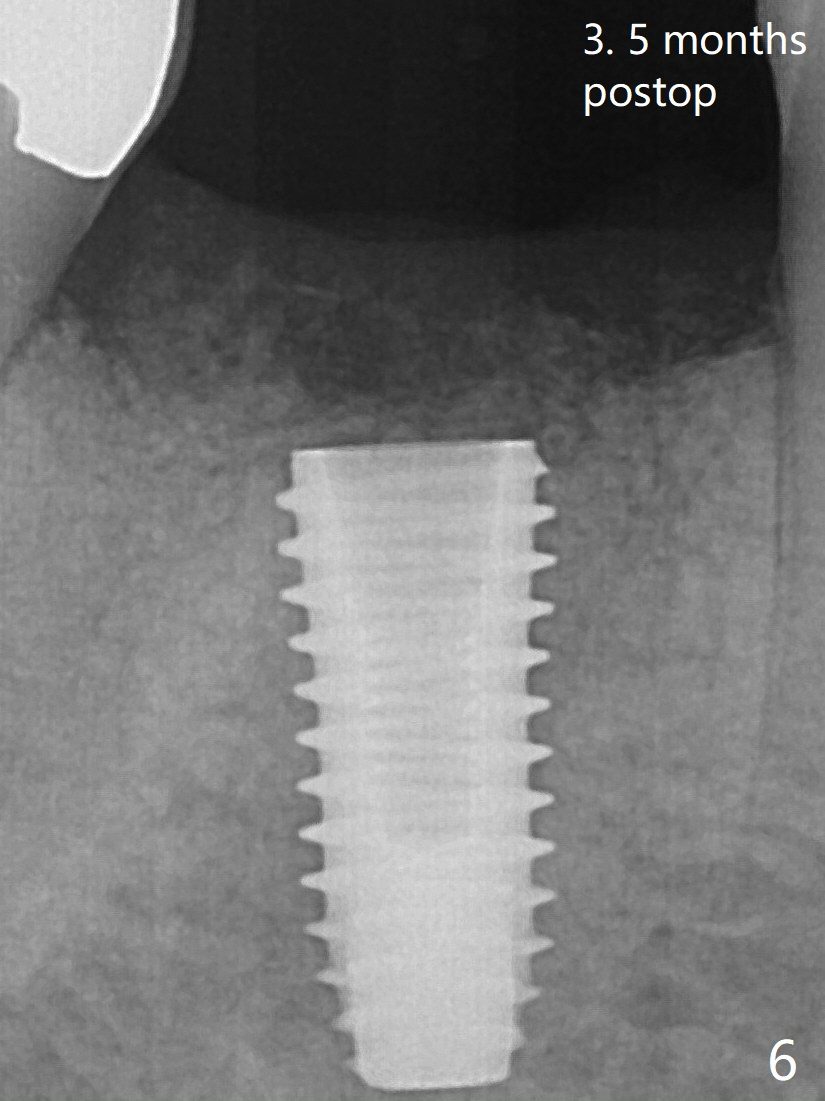

What is ignored is the mesial deviation of the initial osteotomy (Fig.2 <). The osteotomy shifts to the mesial socket with the next drill. The severity of the deviation is not found until a 5x11.5 mm implant is placed (Fig.3). While Osteogen plug is placed in the apical socket (P), Vanilla (allograft) mixed with Osteogen in the coronal socket (*). Because of tight schedule and partial flap (to remove fractured roots), periodontal dressing is applied around the immediately placed abutment (for retention). An angled abutment may be required before final impression because of the deviated implant. The implant seems to have osteointegrated 3.5 months postop (Fig.6, a month post abutment dislodgement).